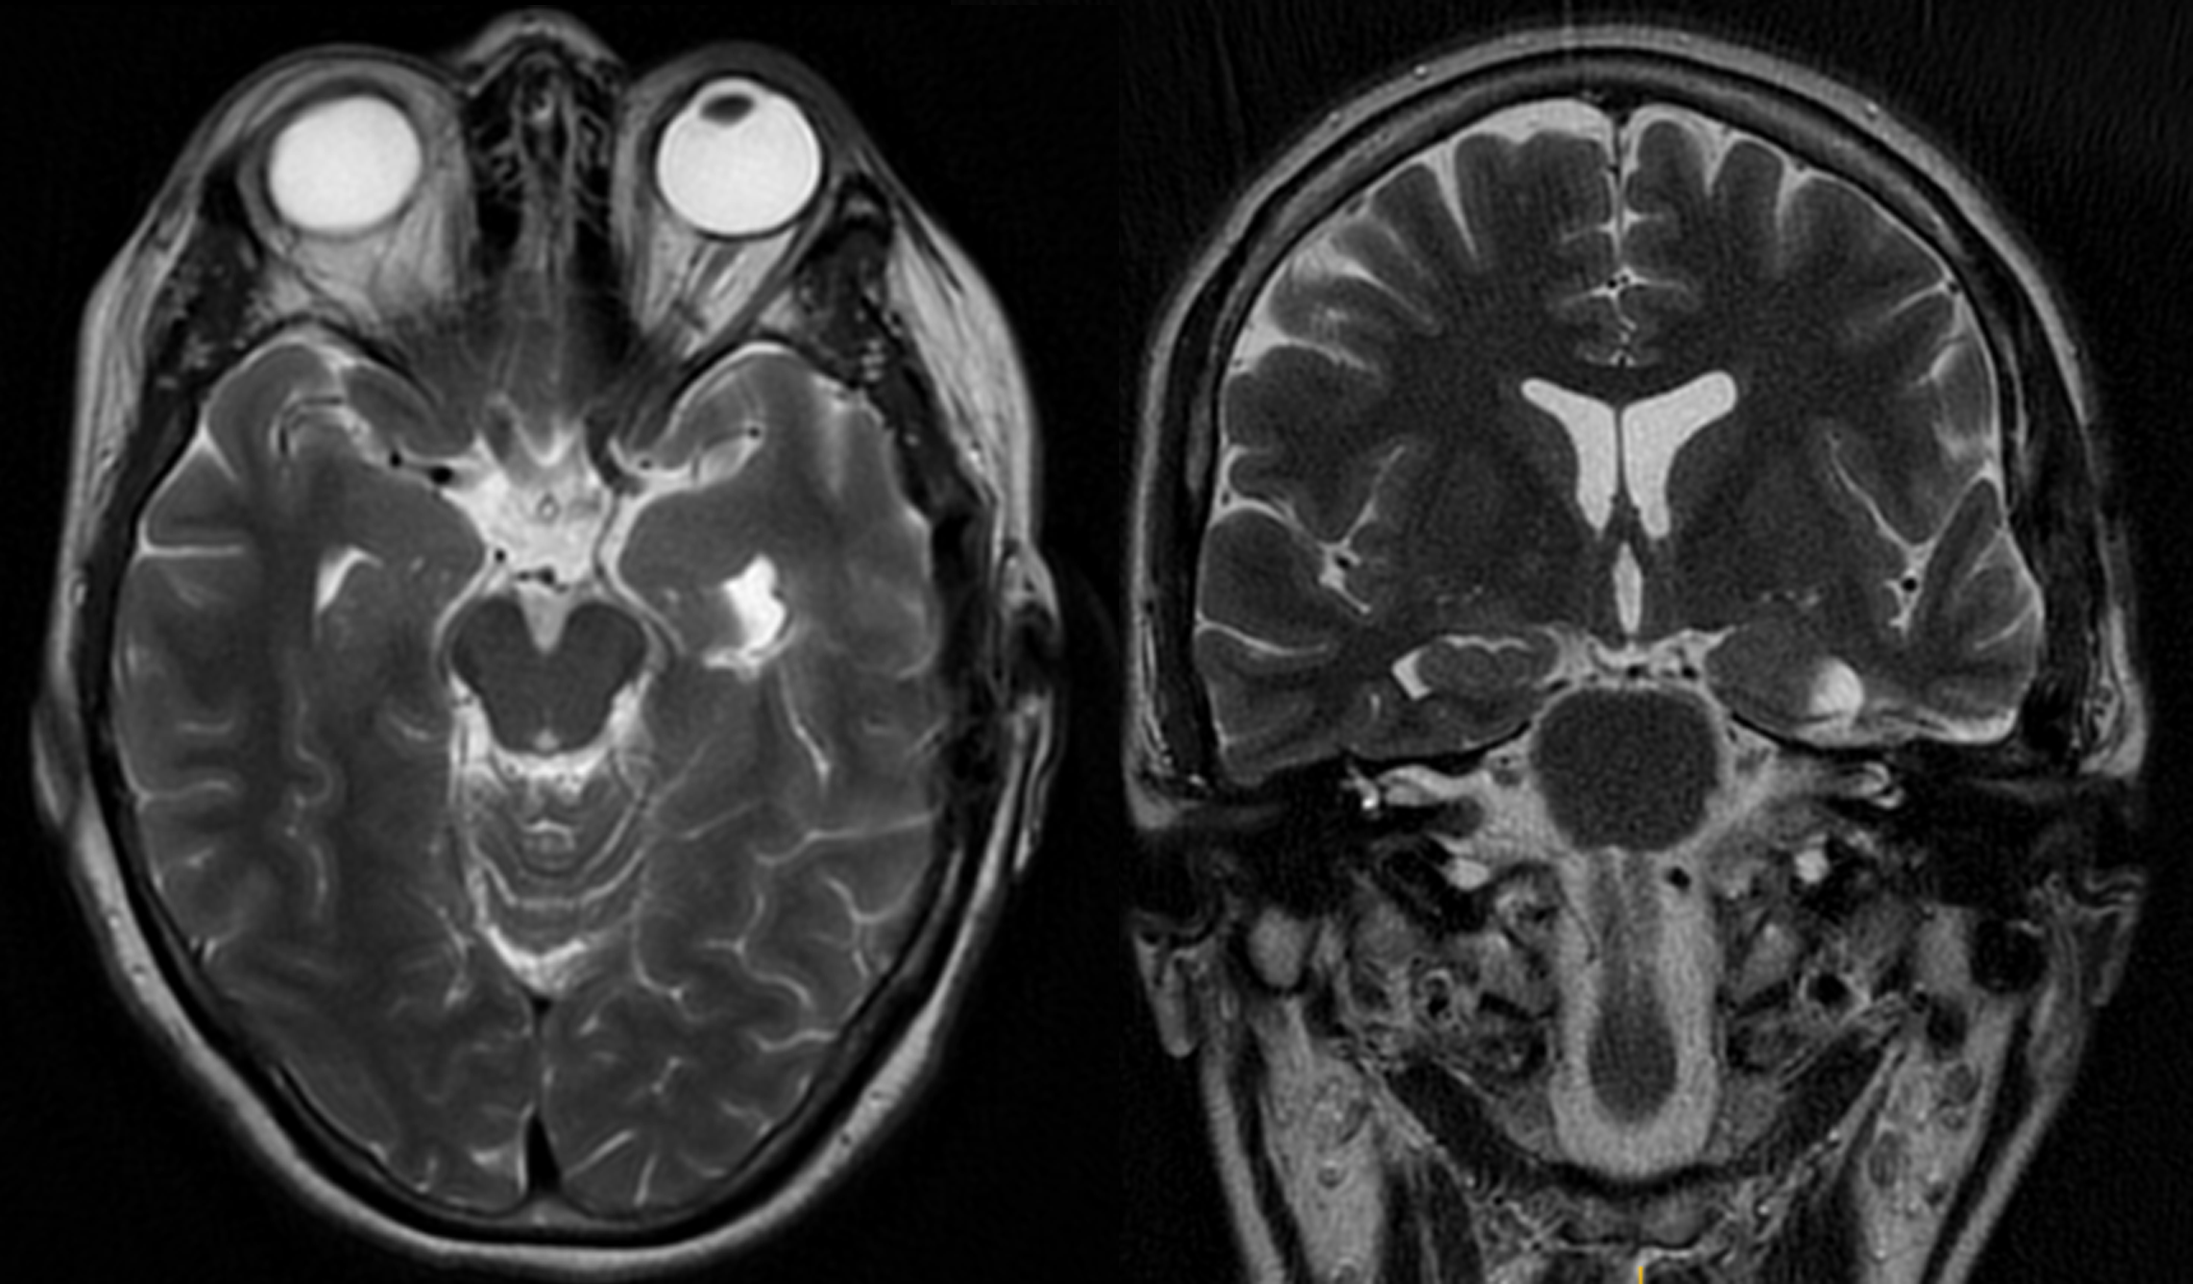

CASO EJEMPLO2: CAVERNOMA INTRA-PARAVENTRICULAR TEMPORAL IZQUIERDO

Fig 1 y 2: Mujer, 48 años, cavernoma incidental.

Fig 3 y 4: Exéresis a través del surco colateral, utilizando un abordaje subtemporal.